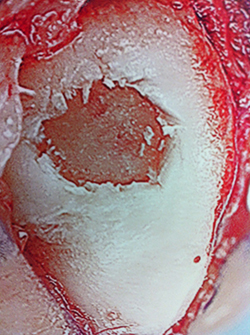

Pic of OCD after preparation and debridement .

Measuring the size and depth of the OCD.